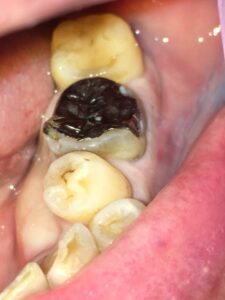

60代男性。左下奥から2番目の銀歯が咬むと痛いことを主訴に来院。

口腔内を診ると、第一大臼歯に大きなアンレー(銀歯)が装着されており、淵の部分のエナメル質が欠けてしまっていました。

保険診療で用いる銀歯は固く、天然歯のほうが負けて欠けてしまい、そこから二次的な虫歯が生じてしまうことがよくあります。

歯に器具をかけると銀歯はすでに浮いており、ポロッととれてきました。幸い銀歯の下にほとんど虫歯はなく、神経までは到達していなかったのでそのまま修復治療を行うことにしました。